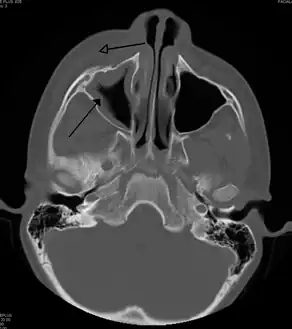

Infection of the eye socket is a rare complication of ethmoid sinusitis, which may result in the loss of sight and is accompanied by fever and severe illness. Another possible complication is the infection of the bones (osteomyelitis) of the forehead and other facial bones – Pott's puffy tumor.[16]

Sinus infection can spread through anastomosing veins or by direct extension to close structures. Orbital complications were categorized by Chandler et al. into five stages according to their severity (see table).[26] Contiguous spread to the orbit may result in periorbital cellulitis, subperiosteal abscess, orbital cellulitis, and abscess. Orbital cellulitis can complicate acute ethmoiditis if anterior and posterior ethmoidal veins thrombophlebitis enables the spread of the infection to the lateral or orbital side of the ethmoid labyrinth. Sinusitis may extend to the central nervous system, where it may cause cavernous sinus thrombosis, retrograde meningitis, and epidural, subdural, and brain abscesses.[27] Orbital symptoms frequently precede intracranial spread of the infection . Other complications include sinobronchitis, maxillary osteomyelitis, and frontal bone osteomyelitis.[28][29][30][31] Osteomyelitis of the frontal bone often originates from a spreading thrombophlebitis. A periostitis of the frontal sinus causes an osteitis and a periostitis of the outer membrane, which produces a tender, puffy swelling of the forehead.

The diagnosis of these complications can be assisted by noting local tenderness and dull pain, and can be confirmed by CT and nuclear isotope scanning. The most common microbial causes are anaerobic bacteria and S. aureus. Treatment includes performing surgical drainage and administration of antimicrobial therapy. Surgical debridement is rarely required after an extended course of parenteral antimicrobial therapy.[32] Chronic sinus infections may lead to mouth breathing, which can result in mouth dryness and an increased risk of gingivitis. Decongestants may also cause mouth dryness.[33]